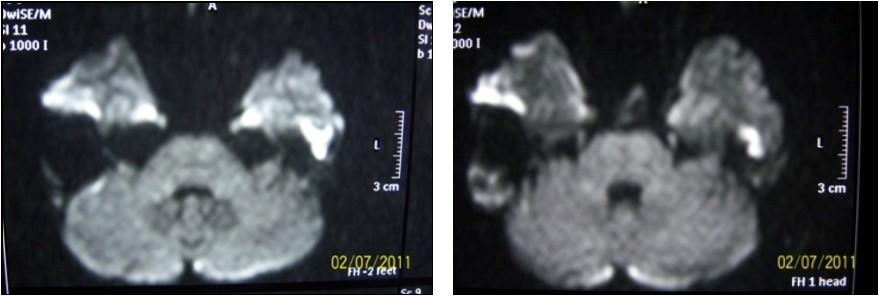

Fındıngs of Preoperatıve Dıffusıon Mrı

High intensity signals on diffusion MRI were considered to be supportive for cholesteatoma (Figure 3). 24 of patients (72.7%) were detected as cholesteatoma positive while 9 of them (27.3%) were negative on diffusion MRI (Table 1).

Figure 3.Diffusion MRI image of cholesteatoma

20 of 24 (83.3%) patients who had signs of cholesteatoma on preoperative diffusion MRI were positive intraoperatively while the remaining 4 (16.7%) were negative. 5 of 9 (55.4%) patients who had no evidence of cholesteatoma on MRI were positive intraoperatively while 4 (44.4%) were not (Table 1). There was no significant result obtained in terms of impact of diffusion MRI on detecting intraoperative cholesteatoma (p=0.09). In terms of indicatory strength of positive physical examination findings over presence of intraoperative cholesteatoma, sensitivity was found to be 96% whereas specifity was 87.5%, positive predictive value was 96% and negative predictive value was 87.5%. The area below the curve on ROC curve analysis was calculated as 98% (Table 3) (Figure 4).